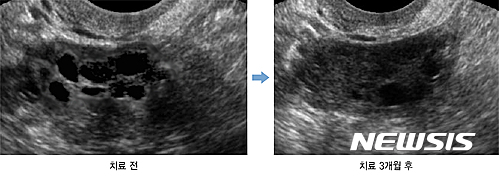

【서울=뉴시스】다낭성난소증후군 치료 전·후 초음파 사진

25일 강동경희대한방병원에 따르면 박경선 한방부인과 교수가 다낭성난소증후군을 진단 받은 환자를 대상으로 3개월간 한약 복용과 침 치료를 병행한 결과 월경 주기가 67일에서 39일로 정상적으로 돌아왔다.

또한 평소에 자주 겪던 소화불량과 어지러움, 몸의 붓기가 감소하고 골반 초음파 검사에서도 배란이 안 된 채 남아있던 우측 난소의 난포 개수가 현저하게 감소했다.